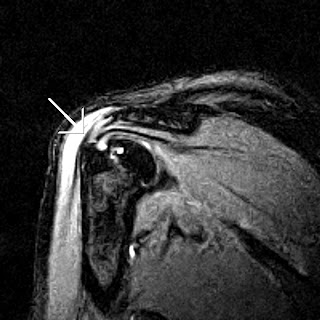

For example, let us discuss someone with a shoulder injury. Let’s say a swimmer has should pain and they are diagnosed with impingement. We've discussed ad nauseum about the presence of structural abnormalities in asymptomatic athletes (See

Radiologic Imaging and the Asymptomatic Athletic Shoulder and

Abnormal MRIs in Tennis Players), but let us pretend the athlete actually has an acute shoulder impingement.